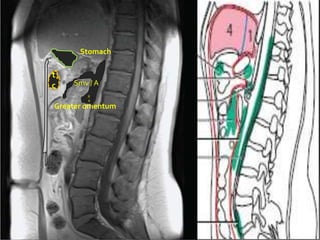

Stomach

t

c   Smv / A

R

A

Greater omentum